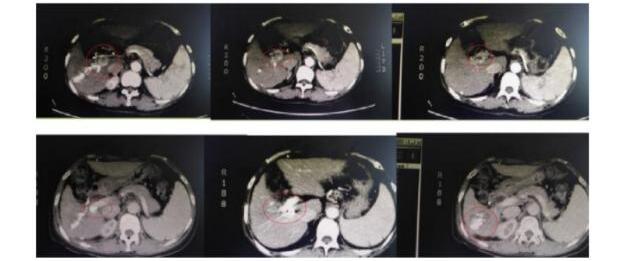

肝癌合并门静脉癌栓患者,可采取TACE、HIAC联合粒子植入并后续靶免联合治疗。

粒子治疗后门静脉通畅癌栓消失,肿瘤完全灭活